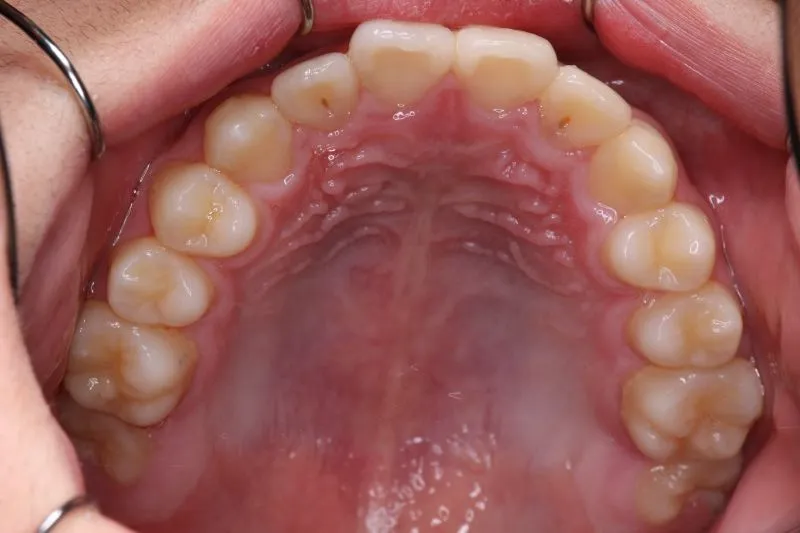

治療終了後

治療回数44回、5年5ヶ月の治療期間で矯正治療を終了しました。

主訴が改善され、ご満足頂きました。